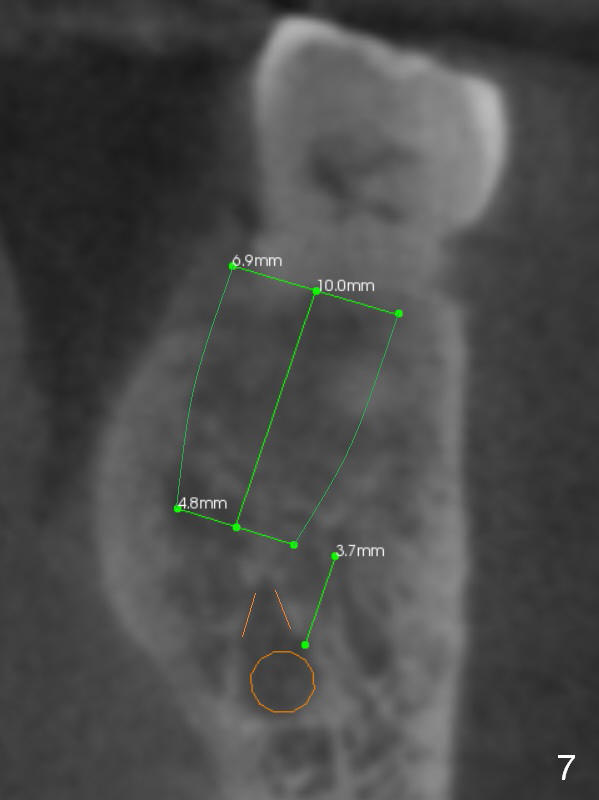

The shorter implant (10 mm (Fig.7 (coronal section)). as compared to 12 mm (Fig.6) more or less placed in the middle of the septum may decrease the chance to penetrate the coronal extension (Fig.8 brown triangle) of the Inferior Alveolar Canal (brown circle).